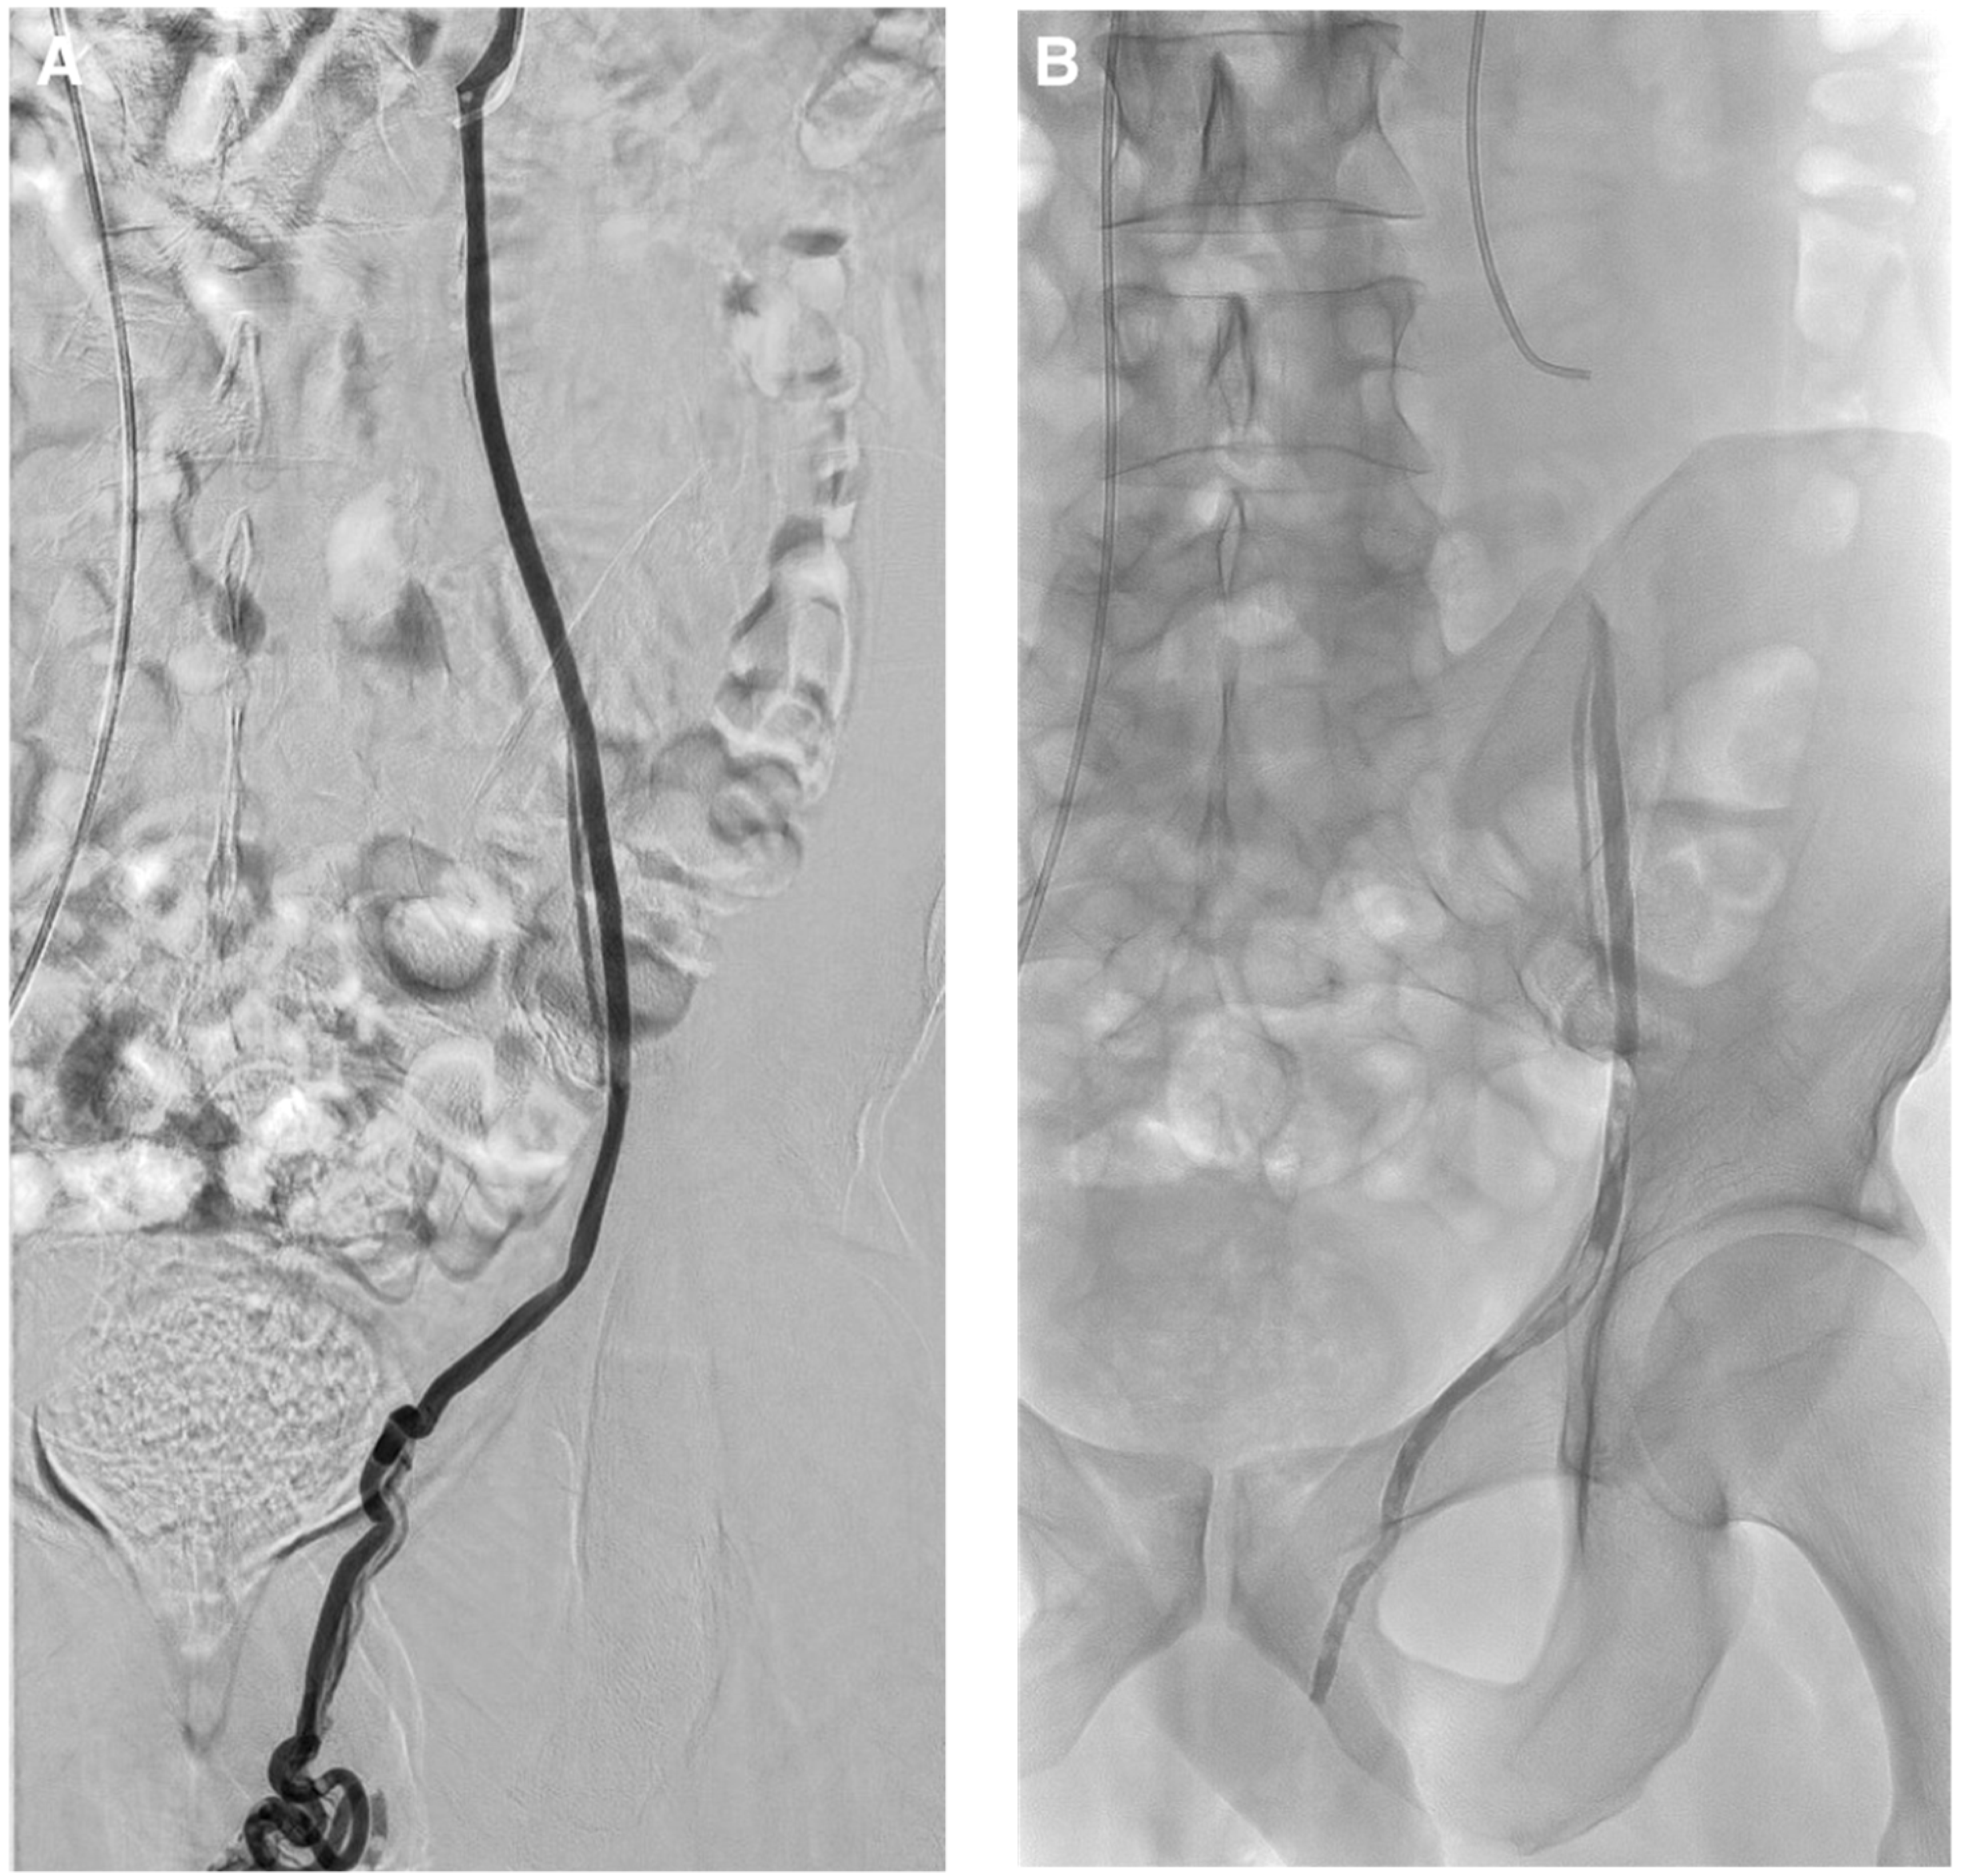

Figure 8. Typical left varicocele embolization with glue. (A) Left gonadal vein phlebography: a 5 French catheter is inserted in the left spermatic vein. A microcatheter is placed below the iliopectineal line and the dead space is filled with dextrose 5%, to avoid intracatheter glue polymerization. Embolization procedure is then performed using glue mixed with lipiodol at a ratio of 1:1 to get fast polymerization and avoid migration in case of reflux. Lipiodol–glue mixture is then injected under strict fluoroscopy, with continuous injection performed manually and a display of real-time distribution. The glue injection begins in the distal intrapelvic segment of the gonadal vein, and the catheter is withdrawn slowly while injecting NBCA under fluoroscopic control. Injection is then stopped before the pampiniform plexus is reached. The microcatheter is then removed when the glue fills the venous space selected beforehand. (B) Here we can see the cast of glue along the left spermatic vein after embolization.